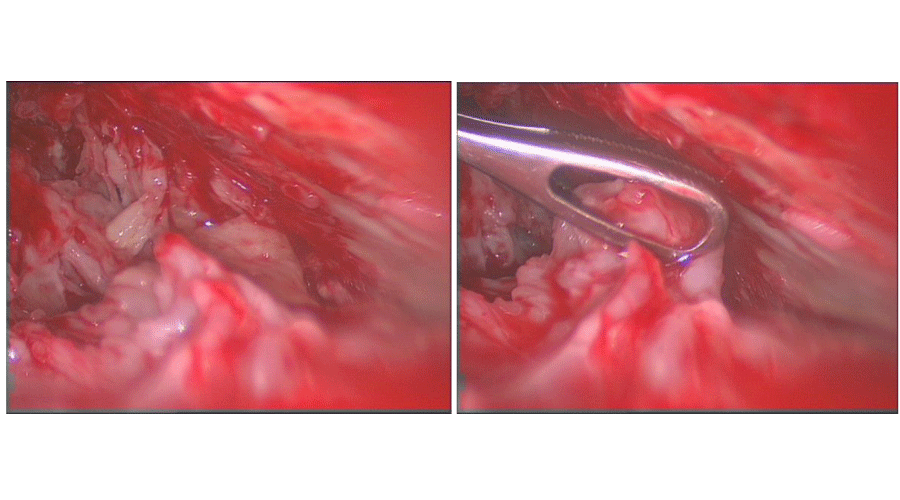

VATS empyema debridement was implemented initially in all cases using a standard two port technique, for simple loculated collections, and three ports where more extensive decortication was required. The inferior 10mm port is used for the camera while a larger anterior incision is used as a utility port. Following drainage of any effusion, the lung is mobilised from the chest wall using a combination of blunt dissection and diathermy for dense adhesions. Sponge-holding forceps can then be used via the utility port to remove fibrinous debris (Figure 2). Copious wash-out of the pleural cavity is performed using betadine solution. At the conclusion of the procedure a size 28 French chest drain is inserted to the apex via the utility port, while a size 32 French chest drain can be passed through the camera port to the base. The lung is re-inflated under direct vision prior to closure.

Figure 2: